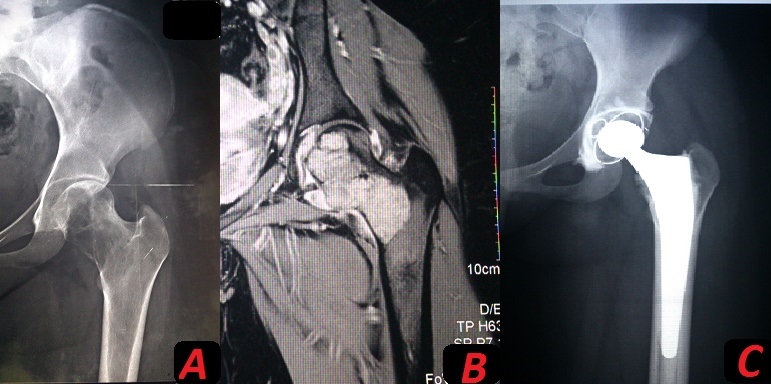

Tumeur à cellules géantes du fémur proximal traitée par arthroplastie totale de hanche

Les auteurs rapportent le cas d'une tumeur à cellules géantes grade 1 de l'extrémité supérieure du fémur, diagnostiquée chez une jeune patiente de 18 ans. Le diagnostic a été suspecté sur une imagerie standard complétée par une IRM est a été confirmé sur une étude histologique après biopsie. La tumeur avait une localisation épiphyso-métaphysaire dépassant le niveau de coupe fémoral sur la planification préopératoire. La prise en charge avait combiné deux techniques chirurgicales, avec une résection marginale de la tête et du col fémoral, et un curetage comblement de la région métaphysaire fémorale avec mise en place d'une PTH cimentée. Le résultat est très satisfaisant avec une bonne récupération fonctionnelle sans aucun signe de récidive après un recul de 2 ans.